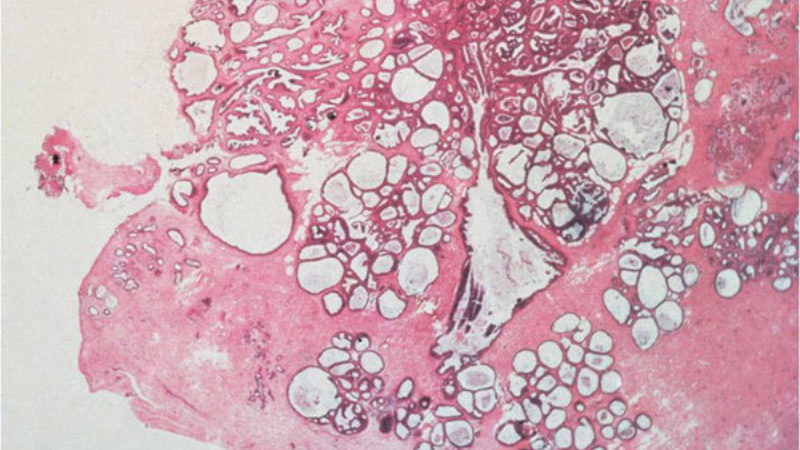

A rare type of fibroepithelial lesion of the breast that contains neoplastic stromal cells and associated benign epithelium. Phyllodes tumors differ from fibroadenomas because they are more cellular and have a unique “leaf-like” pattern of growth. Phyllodes tumors can be benign, borderline (i.e., in between benign and malignant), or malignant and all require surgical excision.

A category of tumors that have contain proliferations of both stromal and epithelial cells. This category includes fibroadenoma and phyllodes tumor.

A benign breast lesion containing both the stromal and epithelial cells. Fibroadenomas are the most common type of fibroepithelial lesion of the breast, and they are most common in young adult women. Fibroadenomas do not require surgical excision, but they may be excised if they are growing or symptomatic such as causing pain.